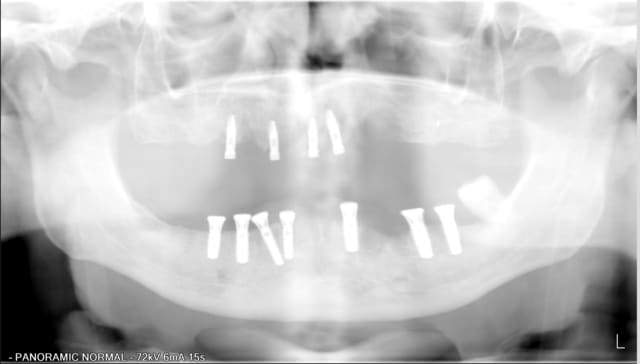

En 2009 extraction de la 37 suite pb paro +++

pas de radio lors des controle suivants, mais mise en place de parocline a plusieurs reprises autour des implants mandibulaires.

aujourd'hui on a des lésions importantes autour de 13 mais pas de perte de volume de tissu gingival, ou tres peu mais je ne pense pas pouvoir réenfouir (SPLINE)

en bas je ne pense pas pouvoir demonter la prothèse

En bas, je suppose plus une infection paro transmise par la proximité de la 37 qui est restée 2 ans en bouche après la pose des implants.

Ton analyse me semble relativement bonne. Par contre, je le dis souvent, je pense que c'est aussi et surtout (malheureusement) un problème occlusal.

Sur les panos la courbe ne semble pas bonne. Elle devrait appraitre rectiligne ou inverse de celle que l'on observe et ce quelque soit le positionnement de la personne.

par contre, les implants en 36/37 sont amha perdus...

j'ai un gros doute sur 36 37

le patient n'aurait pas bouger lors de la pano

je prendrais une rétro avant décision de couper